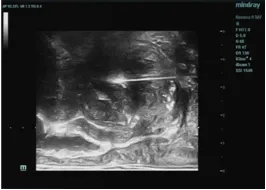

消融中

消融后即刻超声造影评估,呈“空洞状”

在术中,经验丰富的郭建琴主任医师团队借助先进的经直肠双平面超声探头精准引导,通过一根直径仅1.4mm的微波消融针,经会阴部精准穿刺至前列腺增生部位——直达病灶深处,利用超声实时监控,医生精准的将微波针在病灶中移动,术中不能有丝毫差错,在保证不伤到尿道、外周组织、血管及神经的同时,让微波能量精准的使增生组织凝固性坏死,整个过程创伤小,极大降低了对患者身体机能的影响。

术后超声造影即刻评价治疗效果显示,目标增生组织被精准消融,术中出血极少,体表仅轻微针眼,患者安返病房。术后患者恢复良好,排尿功能显著改善,肾功能指标也趋于稳定出院。